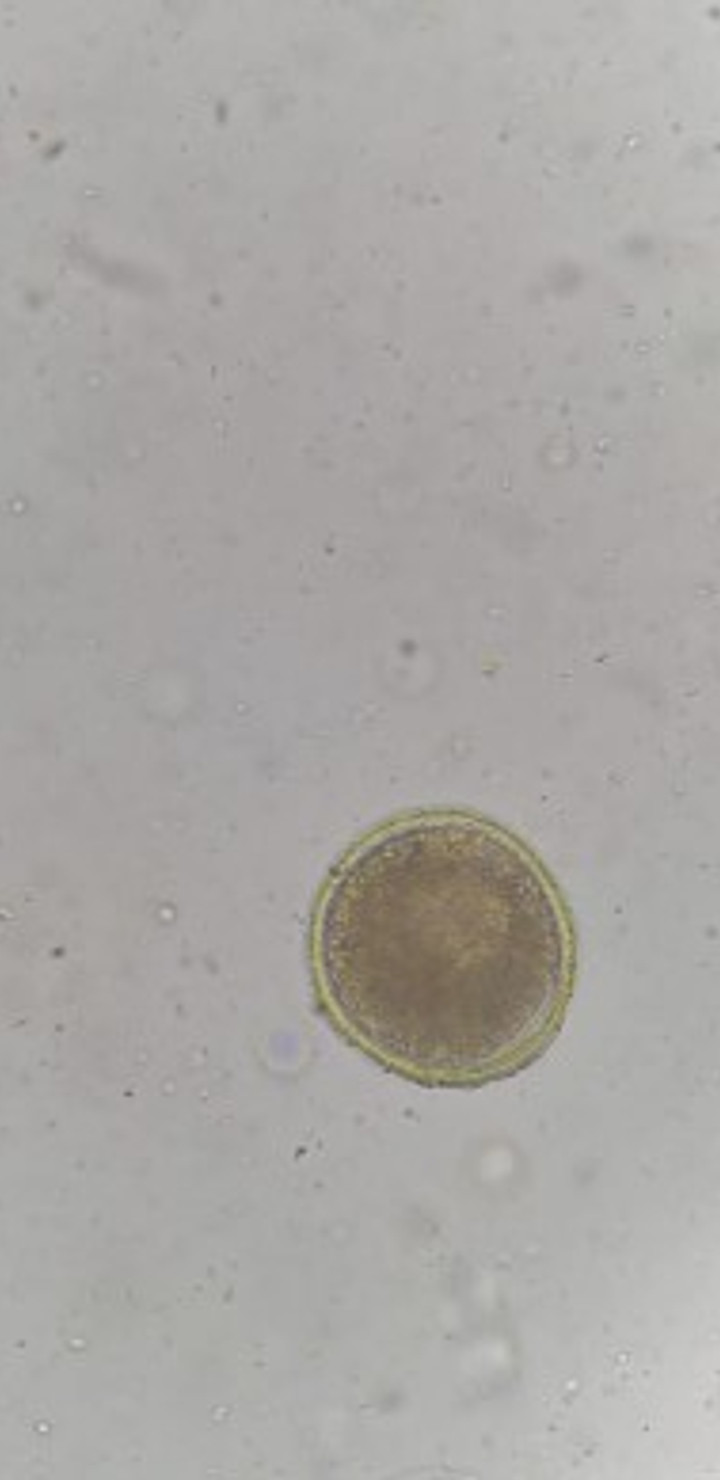

Berdasarkan penelitian Sasmita dkk (2019) yang menggunakan 46 sampel feses kucing di Kec. Sawahan Surabaya menemukan 2 jenis caing yang bersifat zoonosis yaitu Ancylostoma sp dan Toxocara cati.

Sedangkan berdasarkan hasil penelitian Wardhani dkk (2021) yang menggunakan 100 sampel feses kucing di kota Surabaya, diperoleh data prevalensi telur cacing pada kucing liar sebanyak 52% dan kucing peliharaan sebanyak 8%. Jenis telur cacing yang paling banyak ditemukan adalah Toxocara cati dan Ancylostoma sp.

Kemudian berdasarkan penelitian yang dilakukan oleh Rohmayani, dkk (2022) yang menggunakan 100 sampel feses kucing di kota Surabaya, diperoleh data prevalensi infeksi cacing pada feses kucing seacar keseluruhan sebesar 35%.

Pada kucing liar didapatkan prevalensi sebesar 60%, sedangkan pada kucing peliharaan didapatkan prevalensi sebesar 10%. Berdasarkan pembagian wilayah, kasus terbanyak ditemukan pada wilayah Surabaya Timur dengan persentase prevalensi parasite cacing sebesar 63%.

Adapun jenis cacing yang berhasil ditemukan dari hasil penelitian Rohmayani dkk (2022) adalah spesies Toxocara cati, Toxocara canis, Ancylostoma sp, dan Diphyllobotthium sp.